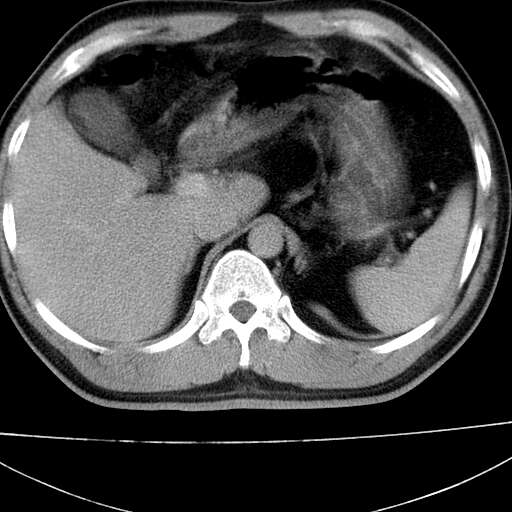

标题: CT21921:腹膜后腔肿物。患者男39Y。体检。增强扫描时间欠准 [打印本页]

标题: CT21921:腹膜后腔肿物。患者男39Y。体检。增强扫描时间欠准

左侧膈肌脚外缘见一结节样软组织影,密度较均匀,与胸膜关系稍密切,增强轻度强化;考虑来自胸膜良性病变(胸膜纤维瘤可能)。建议加扫胸部ct检查。

2、左下膈肌脚外缘结节状病变,与胸膜交界面呈锐角,胸膜下脂肪线可见,定位于肺内,考虑支气管囊肿或肺隔离征可能性大。

膈疝

1)考虑左肺下叶后基底段(或左下胸后壁胸膜)软组织团块,性质待定;建议行进一步检查。2)左肾结石。

左膈肌连续性中断,左侧膈疝可能性大.

左膈肌角后腹膜腔见肿物影,其内见脂肪密度灶及软组织密度灶,强化不明显。病灶大部在后腹膜内。考虑异位嗜铬细胞瘤或脂肪肉瘤、畸胎瘤